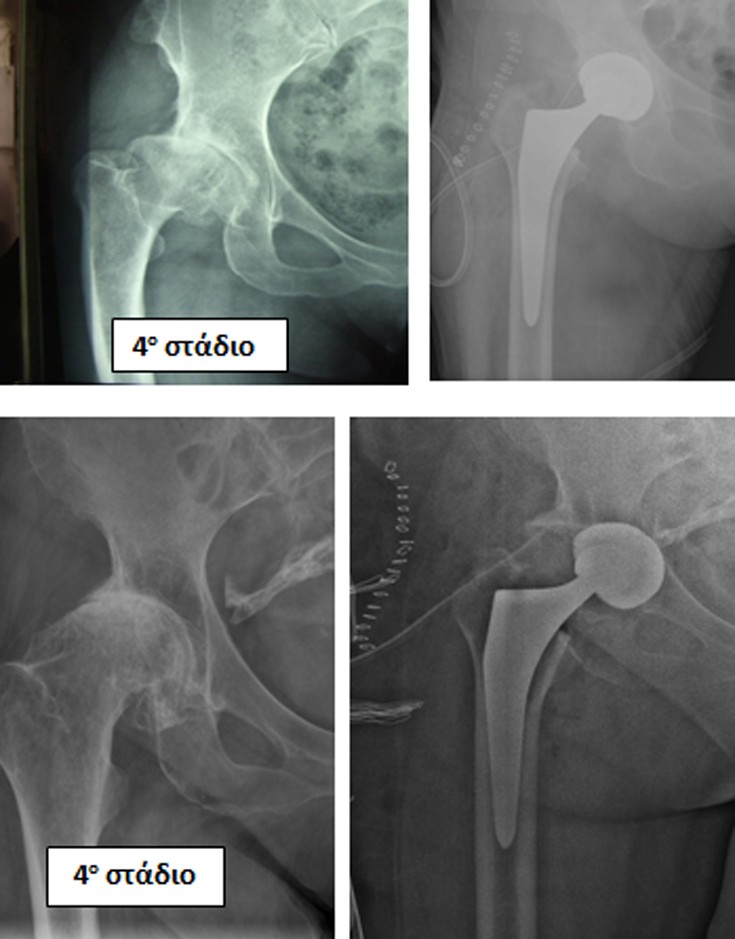

Η οστεοαρθρίτις του ισχίου είναι η κατάληξη όλων των παθήσεων που έχουν ήδη αναφερθεί, δηλ. του συγγενούς εξαρθρήματος, της δυσπλασίας, του CAM, της επιφυσιολίσθησης, του Perthes, της φλεγμονής, του υποκεφαλικού κατάγματος (που διαταράσσει την κυκλοφορία αίματος της κεφαλής), του κατάγματος της κοτύλης, του εξαρθρήματος του ισχίου.